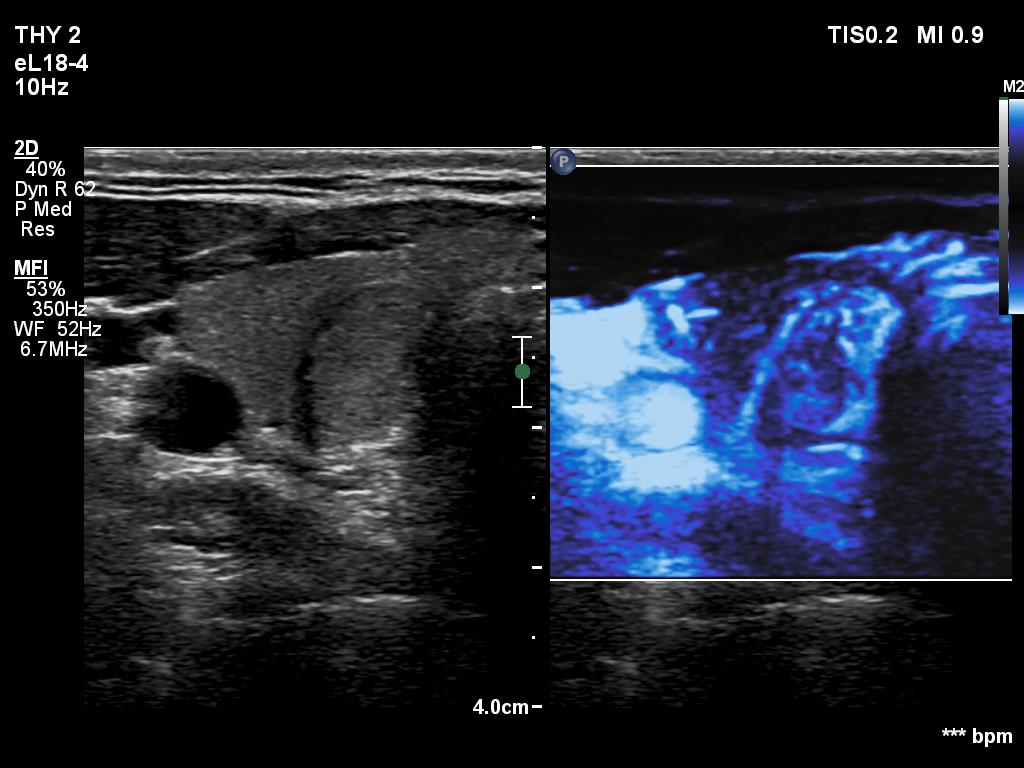

Ultrasonography. The thyroid was echonormal or minimally hypoechogenic. There was an iso/hyperechoic nodule in the right lobe. The lesion had halo and sowed taller-than-wide shape. The vascularity was not specific.

Comments. The nodule is an EU-TIRADS 5 lesion due to the nonparallel orientation.